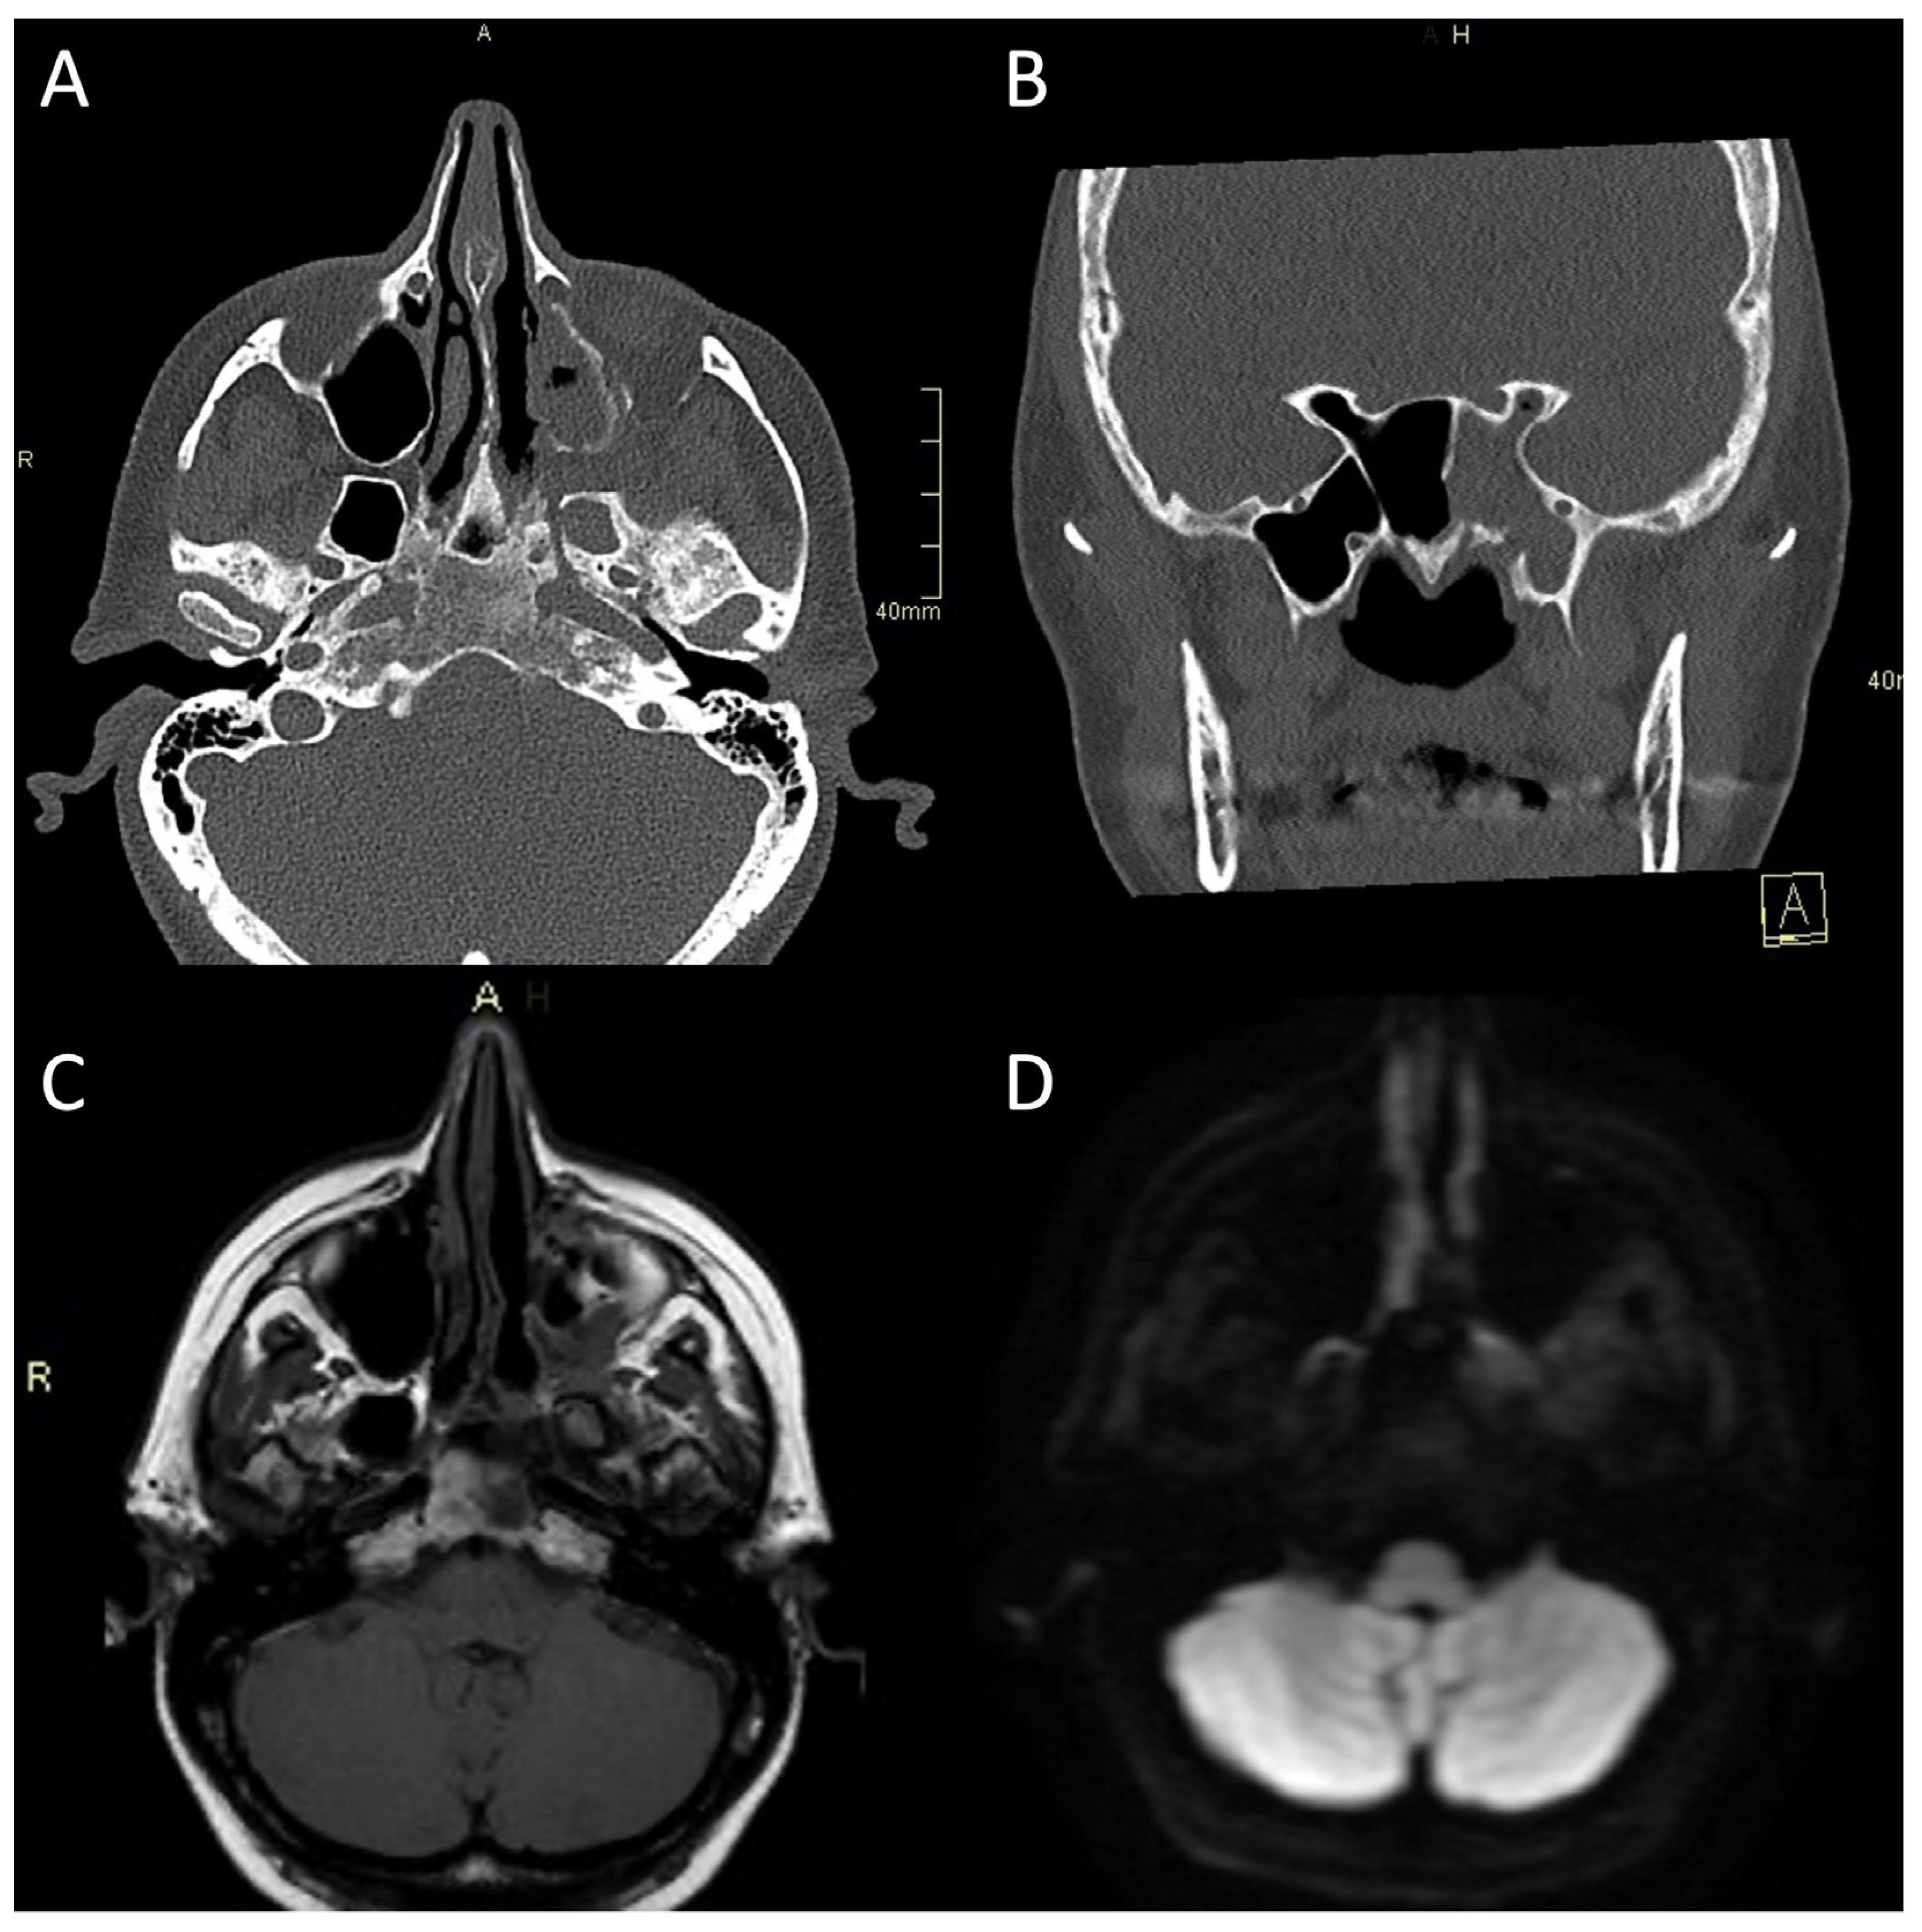

Figure 3.

CT and MRI of a patient with bacterial atypical skull-base osteomyelitis. (A) Axial CT bone algorithm reconstruction showing expanded left pterygopalatine fossa, opacified ipsilateral maxillary, and sphenoid sinus, with mixed erosive and hyperostotic bony changes. (B) Coronal CT bone algorithm reconstruction showing asymmetric expansion and destruction of the left Vidian canal; A—anterior. (C) Axial MRI T1 showing clival bone marrow oedema. (D) Axial MRI DWI showing increased signal in the left pterygoid base, pterygopalatine fossa, and infratemporal fossa. CT: computerised tomography; MRI: magnetic resonance imaging; CE: contrast-enhanced; DWI: diffusion-weighted imaging.

CT is often the first imaging modality in patients with SBO as it is the most accessible and can be performed in the urgent setting. In addition, CT, especially high-resolution bone reformats, is the best way to assess the often subtle bone erosion and demineralisation characteristic of SBO [4,9,18,42]. Cortical erosions in ASBO are most often noted along the anterior clivus and foramina of the central skull base; in cases of invasive sinusitis, opacification and erosion of sinus walls can be noted, especially sphenoid sinus and ethmoid cells (Figure 1A, Figure 2A and Figure 3A,B) [6].

Typical for ASBO is symmetric pre-clival soft tissue involvement, producing nasopharyngeal swelling (Figure 2D,E). In addition, invasive sinus infections have a predilection for spread in the pterygopalatine fossa (Figure 3C,D) [4]. The infection of bone marrow in ASBO results in a loss of normal fat signal, which is seen as T1 hypo-intensity (Figure 2B) and STIR hyperintensity, with heterogenous contrast enhancement of the affected marrow [43,44]. Peripheral contrast enhancement is seen when an abscess is formed in the necrotic part of the bone marrow (Figure 2F,H,I). A combination of abnormal enhancement and absence of contrast enhancement is observed, particularly in mucormycotic infection, indicating the presence of inflammation and necrosis (Figure 4A,B) [45].